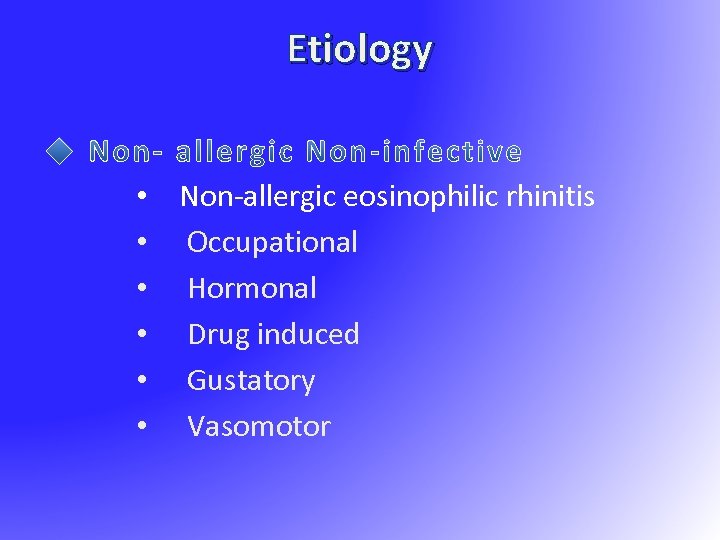

Etiology • Non-allergic eosinophilic rhinitis • Occupational • Hormonal • Drug induced • Gustatory • Vasomotor

Etiology • Non-allergic eosinophilic rhinitis • Occupational • Hormonal • Drug induced • Gustatory • Vasomotor